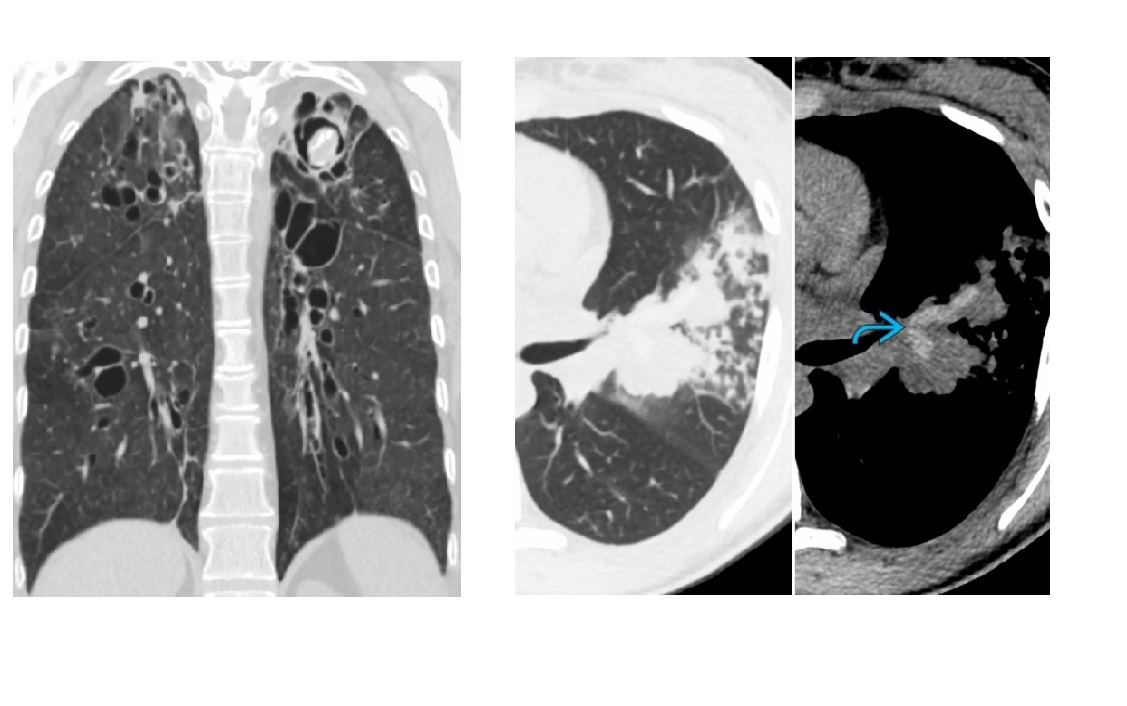

MAC

Tree in bud - terminal bronchiole filled with radiopaque material

cylindric bronchiectasis

clasically right middle lobe or lingula (aka lady windermere syndrome)

Other causes/areas of lung

TB (Pus)

CF, ABPA (mucus)

Cells - Breast and gastric cancer

Aspiration

CMV (bronchial wall thickening)